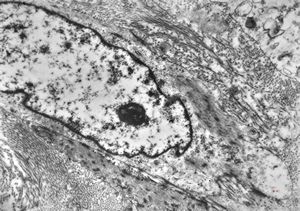

M,52y. | myofibroblastic tumor - pleura